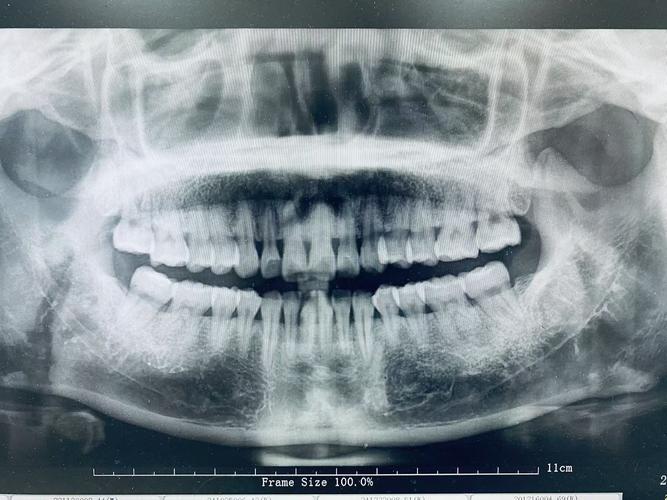

全口曲面断层片(Panoramic Radiograph, OPG)

- 原理与设备:通过X射线管和探测器同步旋转,利用狭缝准直技术对颌骨进行断层摄影,一次曝光即可获取全口牙列、上下颌骨、上颌窦、颞下颌关节等结构的二维影像。

- 临床应用:评估全口牙列情况(如龋病、牙周病、阻生牙、多生牙)、颌骨囊肿或肿瘤、颌骨骨折、正畸治疗前后的牙颌形态分析、种植术前骨量评估。

- 优缺点:优点是辐射剂量低(约0.02mSv)、检查范围广、操作简便;缺点是图像存在一定重叠和变形,对牙齿根尖及细微骨破坏的分辨率低于根尖片,金属修复体易产生伪影。